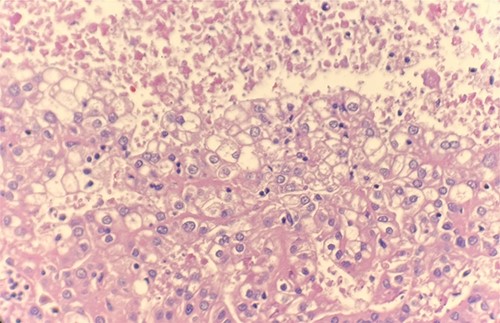

Microscopic examination revealed that clear cell RCC (Fig. 1), papillary RCC type 1 (Fig. 2), and papillary RCC type 2 (Fig. 3) were present in the right kidney, and papillary RCC type 2 was present in both kidneys. Immunostaining showed that tumor cells were positive for alpha-methyacyl-CoA racemase (Fig. 4), CD10, CK7, and vimentin, and negative for CD117.

Microscopic examination reveals pseudostratified tumor cells with papillary architecture, abundant eosinophilic, atypical nuclei and prominent nucleoli. HE stain 40x.